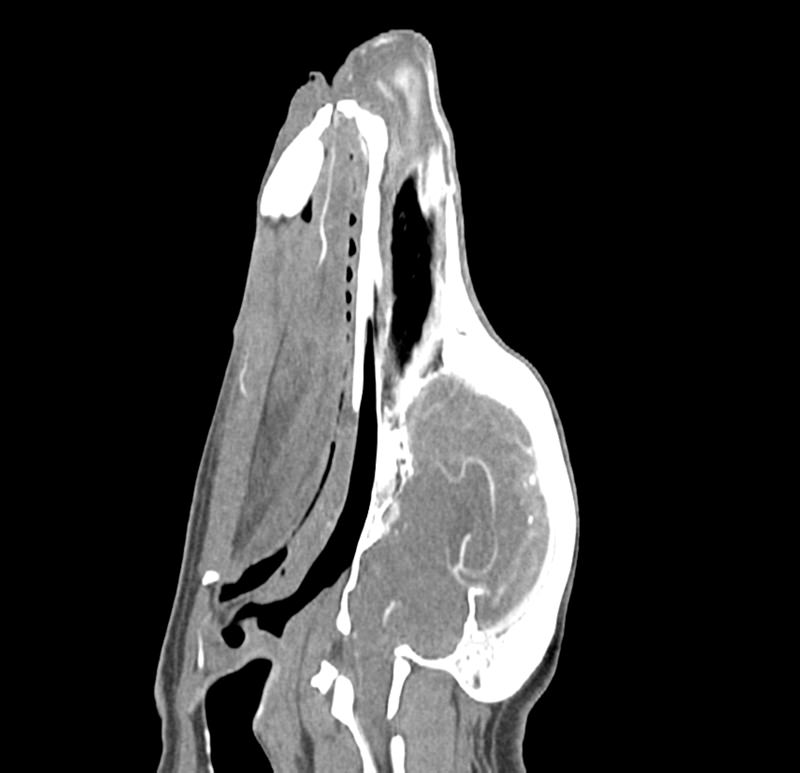

Fantom poskytuje realistickou CT simulaci psí hlavy bez kontrastní látky. Kosti a měkké tkáně jsou autenticky zobrazeny s realistickými hodnotami CT pro všechny tkáně při napětí trubice 120 kVp v CT skeneru. Vzduchové prostory jsou vyplněny kompozitem z celulózového polymeru s přibližně -80 Hounsfieldovými jednotkami. Pokud má být fantom používán primárně při jiném napětím trubice (např. 100 kVp), lze kalibraci hodnot CT v případě potřeby odpovídajícím způsobem upravit. Fantom také poskytuje realistické kontrasty tkání při rentgenovém zobrazování.